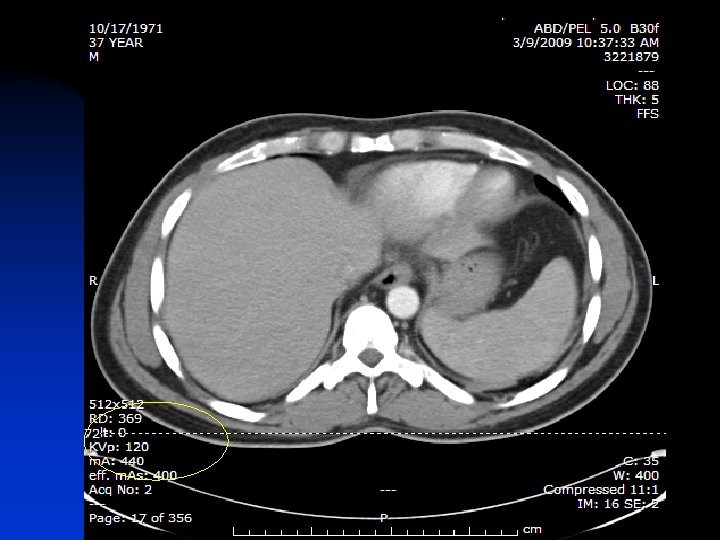

Shock room films: Chest X-ray Lateral C-spine Pelvic film 0. 02 m. Sv 0. 03 m. Sv Trauma Panel: Head CT Cervical Spine Ct Chest CT Abd/pelvic CT 2 m. Sv 8 m. Sv 10 m. Sv Next morning Repeat CT - head T&L spine films Chest Xray 2 m. Sv 0. 1 m. Sv 0. 02 m. Sv Total (first 18 hours) 24. 2 m. Sv

Radiation Exposure for Trauma n n n Winslow et al, Ann Emerg. Med Aug. 2008 n 100 consecutive trauma patients Blunt trauma at a Level I Center Median effective dose of radiation 40. 2 m. Sv Equivalent to 1, 005 chest X-rays

Recommendations n Scan when the data desired will be obtained. n Scan when the data will change management. n Scan at the lowest possible settings to obtain adequate images. Child size the k. Vp ( Kilovolt Peak- Quality ) and m. As (Milliamp second. Quantity)